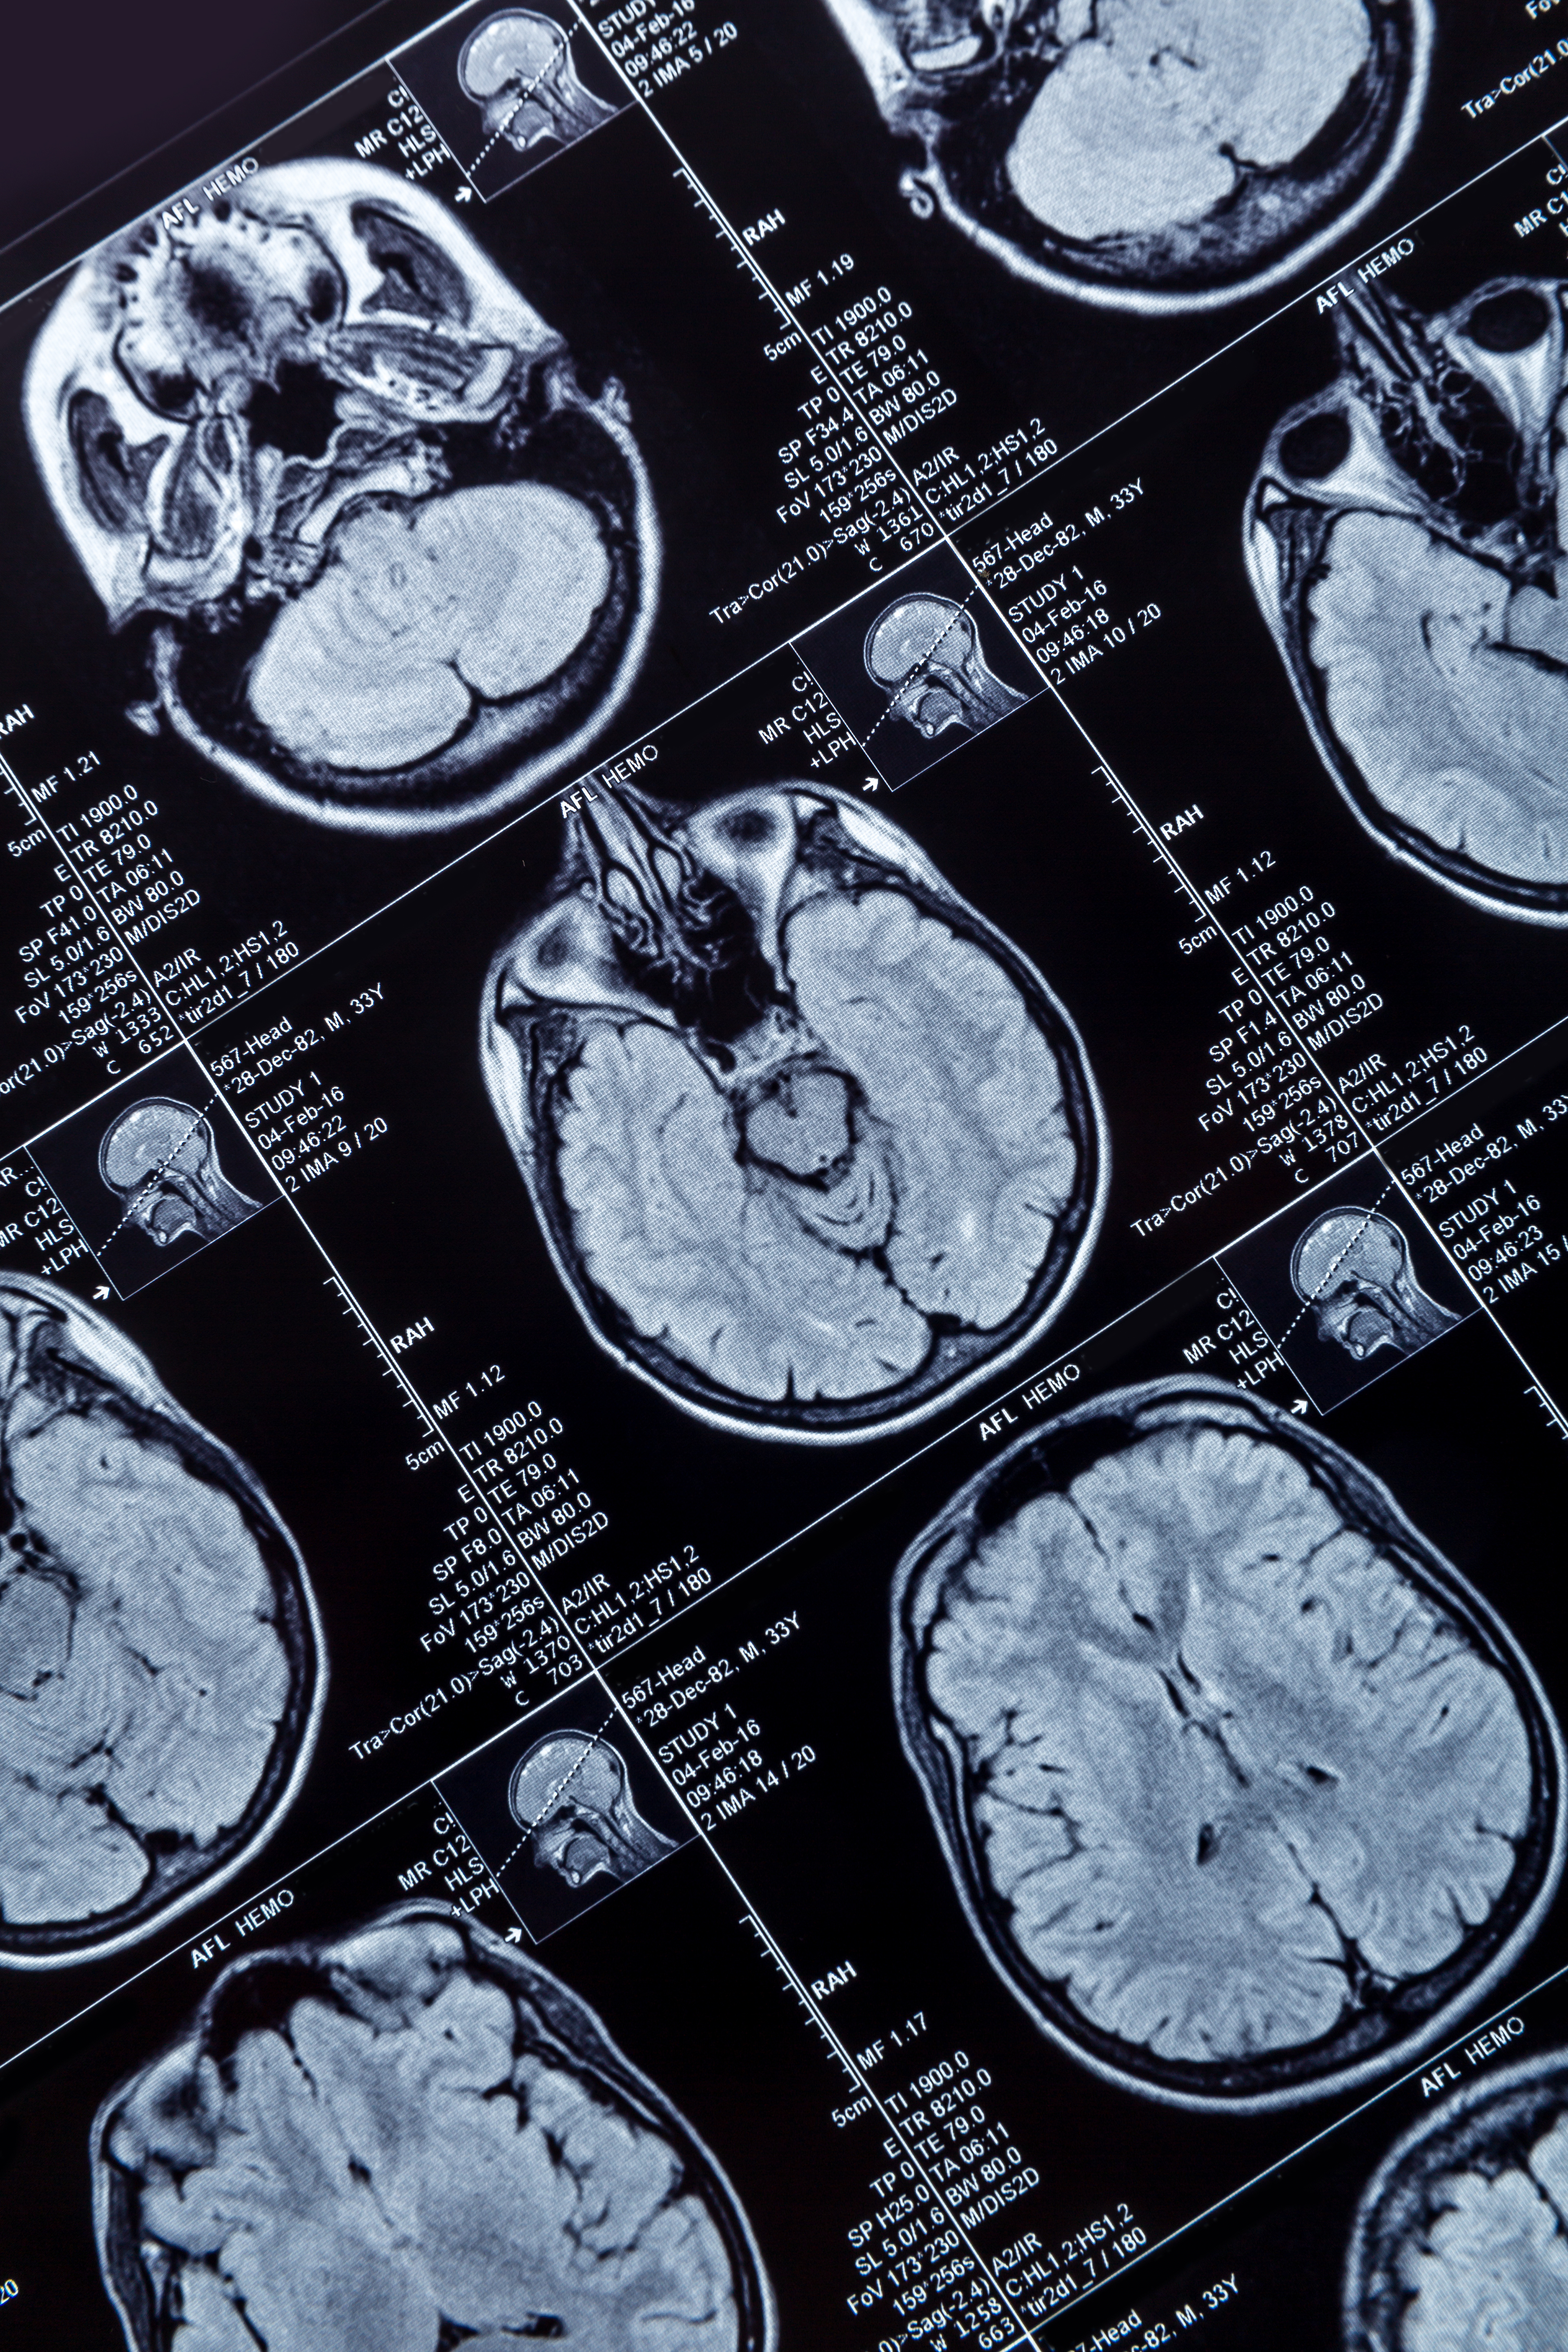

The International Society of Magnetic Resonance in Medicine (ISMRM) will be hosting its annual meeting May 4 to 9 in Singapore. AuntMinnie.com spoke with the society's president, Derek Jones, PhD, director of Cardiff University Brain Research Imaging Center (CUBRIC) in Wales, U.K. about what attendees can expect during the gathering.

ISMRM President Derek Jones, PhD, offers upcoming meeting highlights